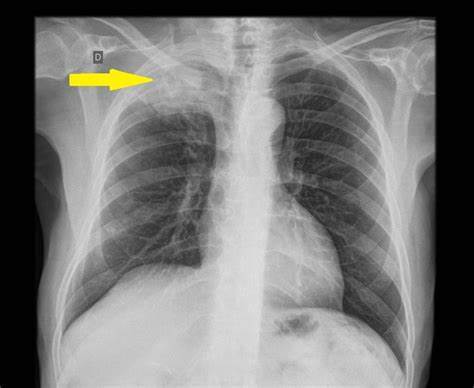

肺上沟癌会导致肩痛

看我们同事母亲ct的时候,谢医生第一眼关注的就是这个位置,肺上沟!因为在这个位置有一种癌症叫做肺上沟癌,是肺癌的一种,会诱发患者出现肩痛,这个癌症的名称并不是由病理分型来确定的,而是由位置决定的,足见它的特殊性!

大家可以把肺上沟这个位置理解为肺部的顶点周边,在这个位置有非常复杂以及重要的结构存在,比如头臂静脉、锁骨下动脉、膈神经、臂丛神经和迷走神经等。

当患者罹患这个位置肿瘤以后,肿瘤如果不是特别的大,这往往不会有任何的症状,甚至都没有肺癌患者常见的咳嗽、呼吸困难、咳痰等表现,症状可以说是非常的隐秘。但是随着肿瘤的生长变得越来越大,肿瘤有可能最终突破肺的表面,侵犯到前面所说的,在肺上沟这个位置非常重要的结构,当侵犯到闭孔神经、胸膜、筋膜、肋骨等结构,就会诱发患者出现尖锐的后背疼,患者的腋窝和肩胛骨的区域也有可能出现剧烈的疼痛,有可能会蔓延到头部、颈部或者是手臂。